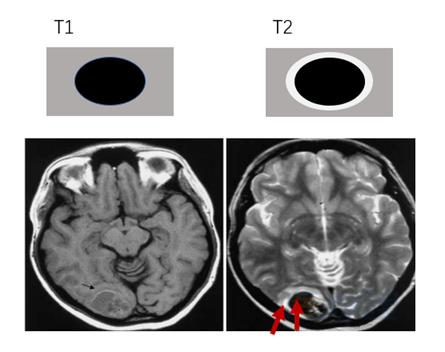

▎慢性期:2周后或3周后

慢性期早期的MRI表现与亚急性晚期相似。之后,血肿内血红蛋白最终被吞噬、分解、移除,留下大量的含铁血黄素。血肿被逐渐吸收或液化,部分形成囊腔,周边可出现明显的含铁血黄素沉积。因此, T1WI上表现为低信号,T2WI上表现为,囊腔或液化灶呈高信号,可出现周围含铁血黄素低信号环。慢性期水肿消退。

需要注意的是,脑出血的演进是一个连续的过程,在亚急性晚期,可出现血肿周围的高铁血红蛋白被巨噬细胞吞噬,形成含铁血黄素沉积,表现为环绕在血肿周围的T1、T2低信号环,这时,亚急性晚期和慢性期早期其实有相似的表现,不太容易区分。